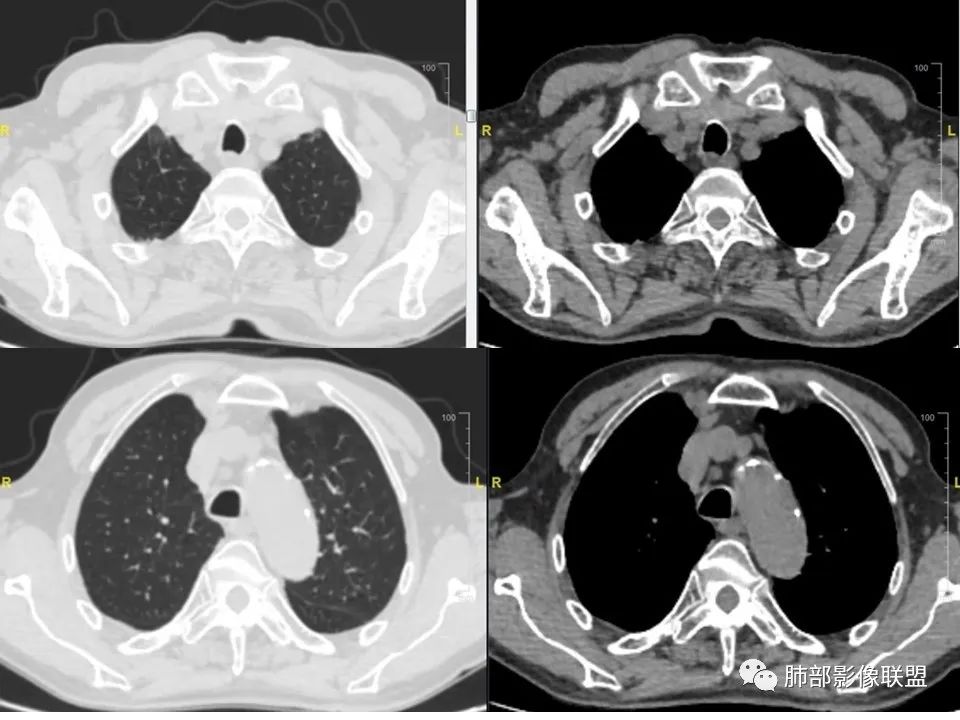

三明治征”之谜—胸膜淋巴瘤1例CT影像

老年男性,右侧胸膜软组织肿块延伸至后纵隔主动脉旁,平扫密度均匀稍高,增强扫描均匀强化,高于肌肉,其内血管走形包绕,部分包绕肋骨,考虑淋巴瘤。病人石棉接触史,不能除外间皮瘤(胸水应该更多)。

右肺下叶肿块,宽基底与胸膜相连,局部胸膜下间隙消失,肋骨未见明显骨质破坏,平扫密度均匀,增强后可见内部点片状强化,坏死囊变不明显,右肺叶裂旁多个小气囊,双肺多发模糊的小结节,老年男性,有石棉肺,综合考虑1:胸膜间皮瘤2:淋巴瘤3:结核瘤4:SFT

老年男性,咳嗽气喘纳差3个月,慢性病史,有石棉接触史。右下肺胸膜下巨大肿块,宽基底与胸膜相连,考虑来源胸膜,密度均匀,内有钙化,左侧胸膜增厚,有点状钙化,双肺野外带可见斑片影,多发囊泡,考虑恶性胸膜间皮瘤,慢阻肺。 医学百科网 | YxBaike.Com

患者老年男性,咳嗽、气喘、纳差3月(近3月体重下降10斤),既往史:中年时期有石棉接触史2年。慢性支气管炎病史6年,胆囊炎手术病史9年。心律不齐病史9年,脑梗塞病史2年余,血沉91mm/h。胸CT:右侧胸膜明显增厚,4R 7组淋巴结肿大。考虑恶性胸膜间皮瘤。